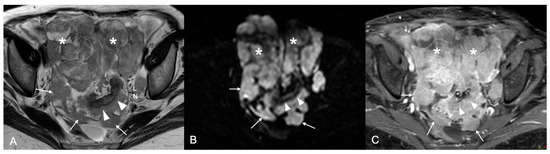

Figure 1